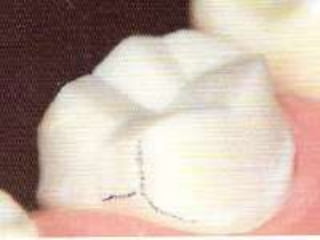

CORONAS DE RECUBRIMIENTO PARCIAL – 7/8Indicaciones:Dientes con cúspide MV intacta pero con restauracionesPrimeros molares superiores, con restauración extensa distal o distovestibularRetención y resistencia significativamente mayor que la corona 3/4

La reducción es de 1 mm en las cúspides no funcionales y en las funcionales de 1,5 mm